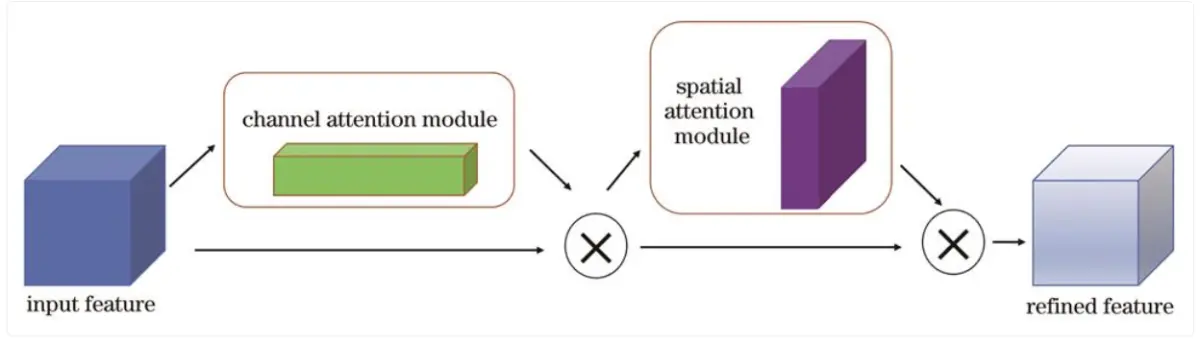

10.卷积块注意力模块

卷积块注意力模块结合了通道注意力机制与空间注意力机制,相较于只关注通道域的SE模块,CBAM在通道域和空间域两个维度推算注意力图,可筛选出更重要的语义特征,因此可以取得更好的效果,具体结构如图所示。

首先将特征图输入到通道注意力模块中得到对应通道的权重,得到加权结果后将加权后的特征图输入空间注意力模块中得到对应权重,加权后输出特征图,计算方法表示为: